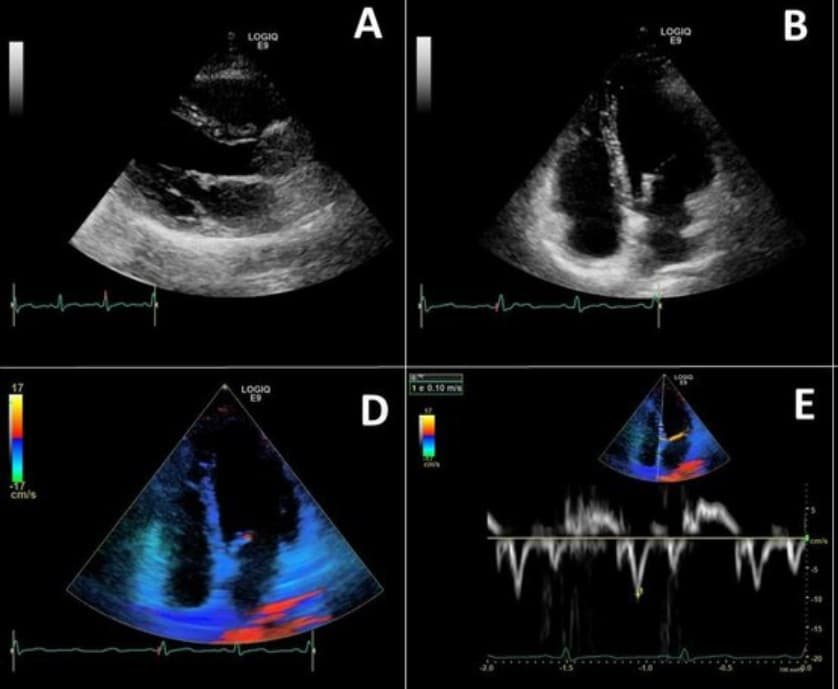

- Echocardiogram